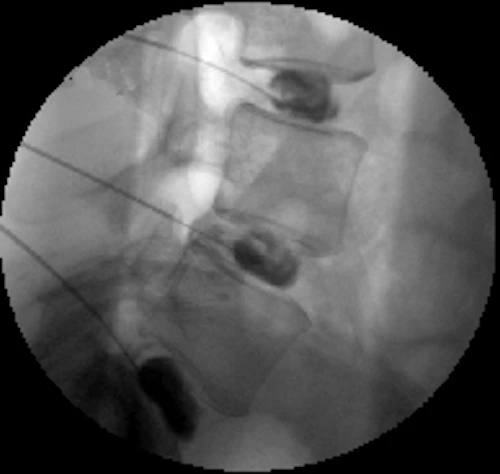

The exact level is located with the fluoroscope, and the skin overlying this area is anesthetized (numbed) with lidocaine. This is either to the right or left of midline on the back.

A needle is sterilely advanced along the nerve root sleeve, which typically elicits a mild degree of radicular pain in the distribution of that nerve. It is important for us to know whether the pain elicited is similar to the patient’s pain (concordant response), or dissimilar (discordant response).

Typically, as small amount of water-soluble contrast (dye) is injected to confirm proper needle tip position.

This procedure may be performed with either CT or Fluoroscopic guidance.